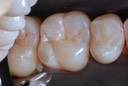

Photos of Clinical Operations

Drs. Peter Kearney, Terry McKay, John St. Germain, and Laurie Vanzella - Mentors